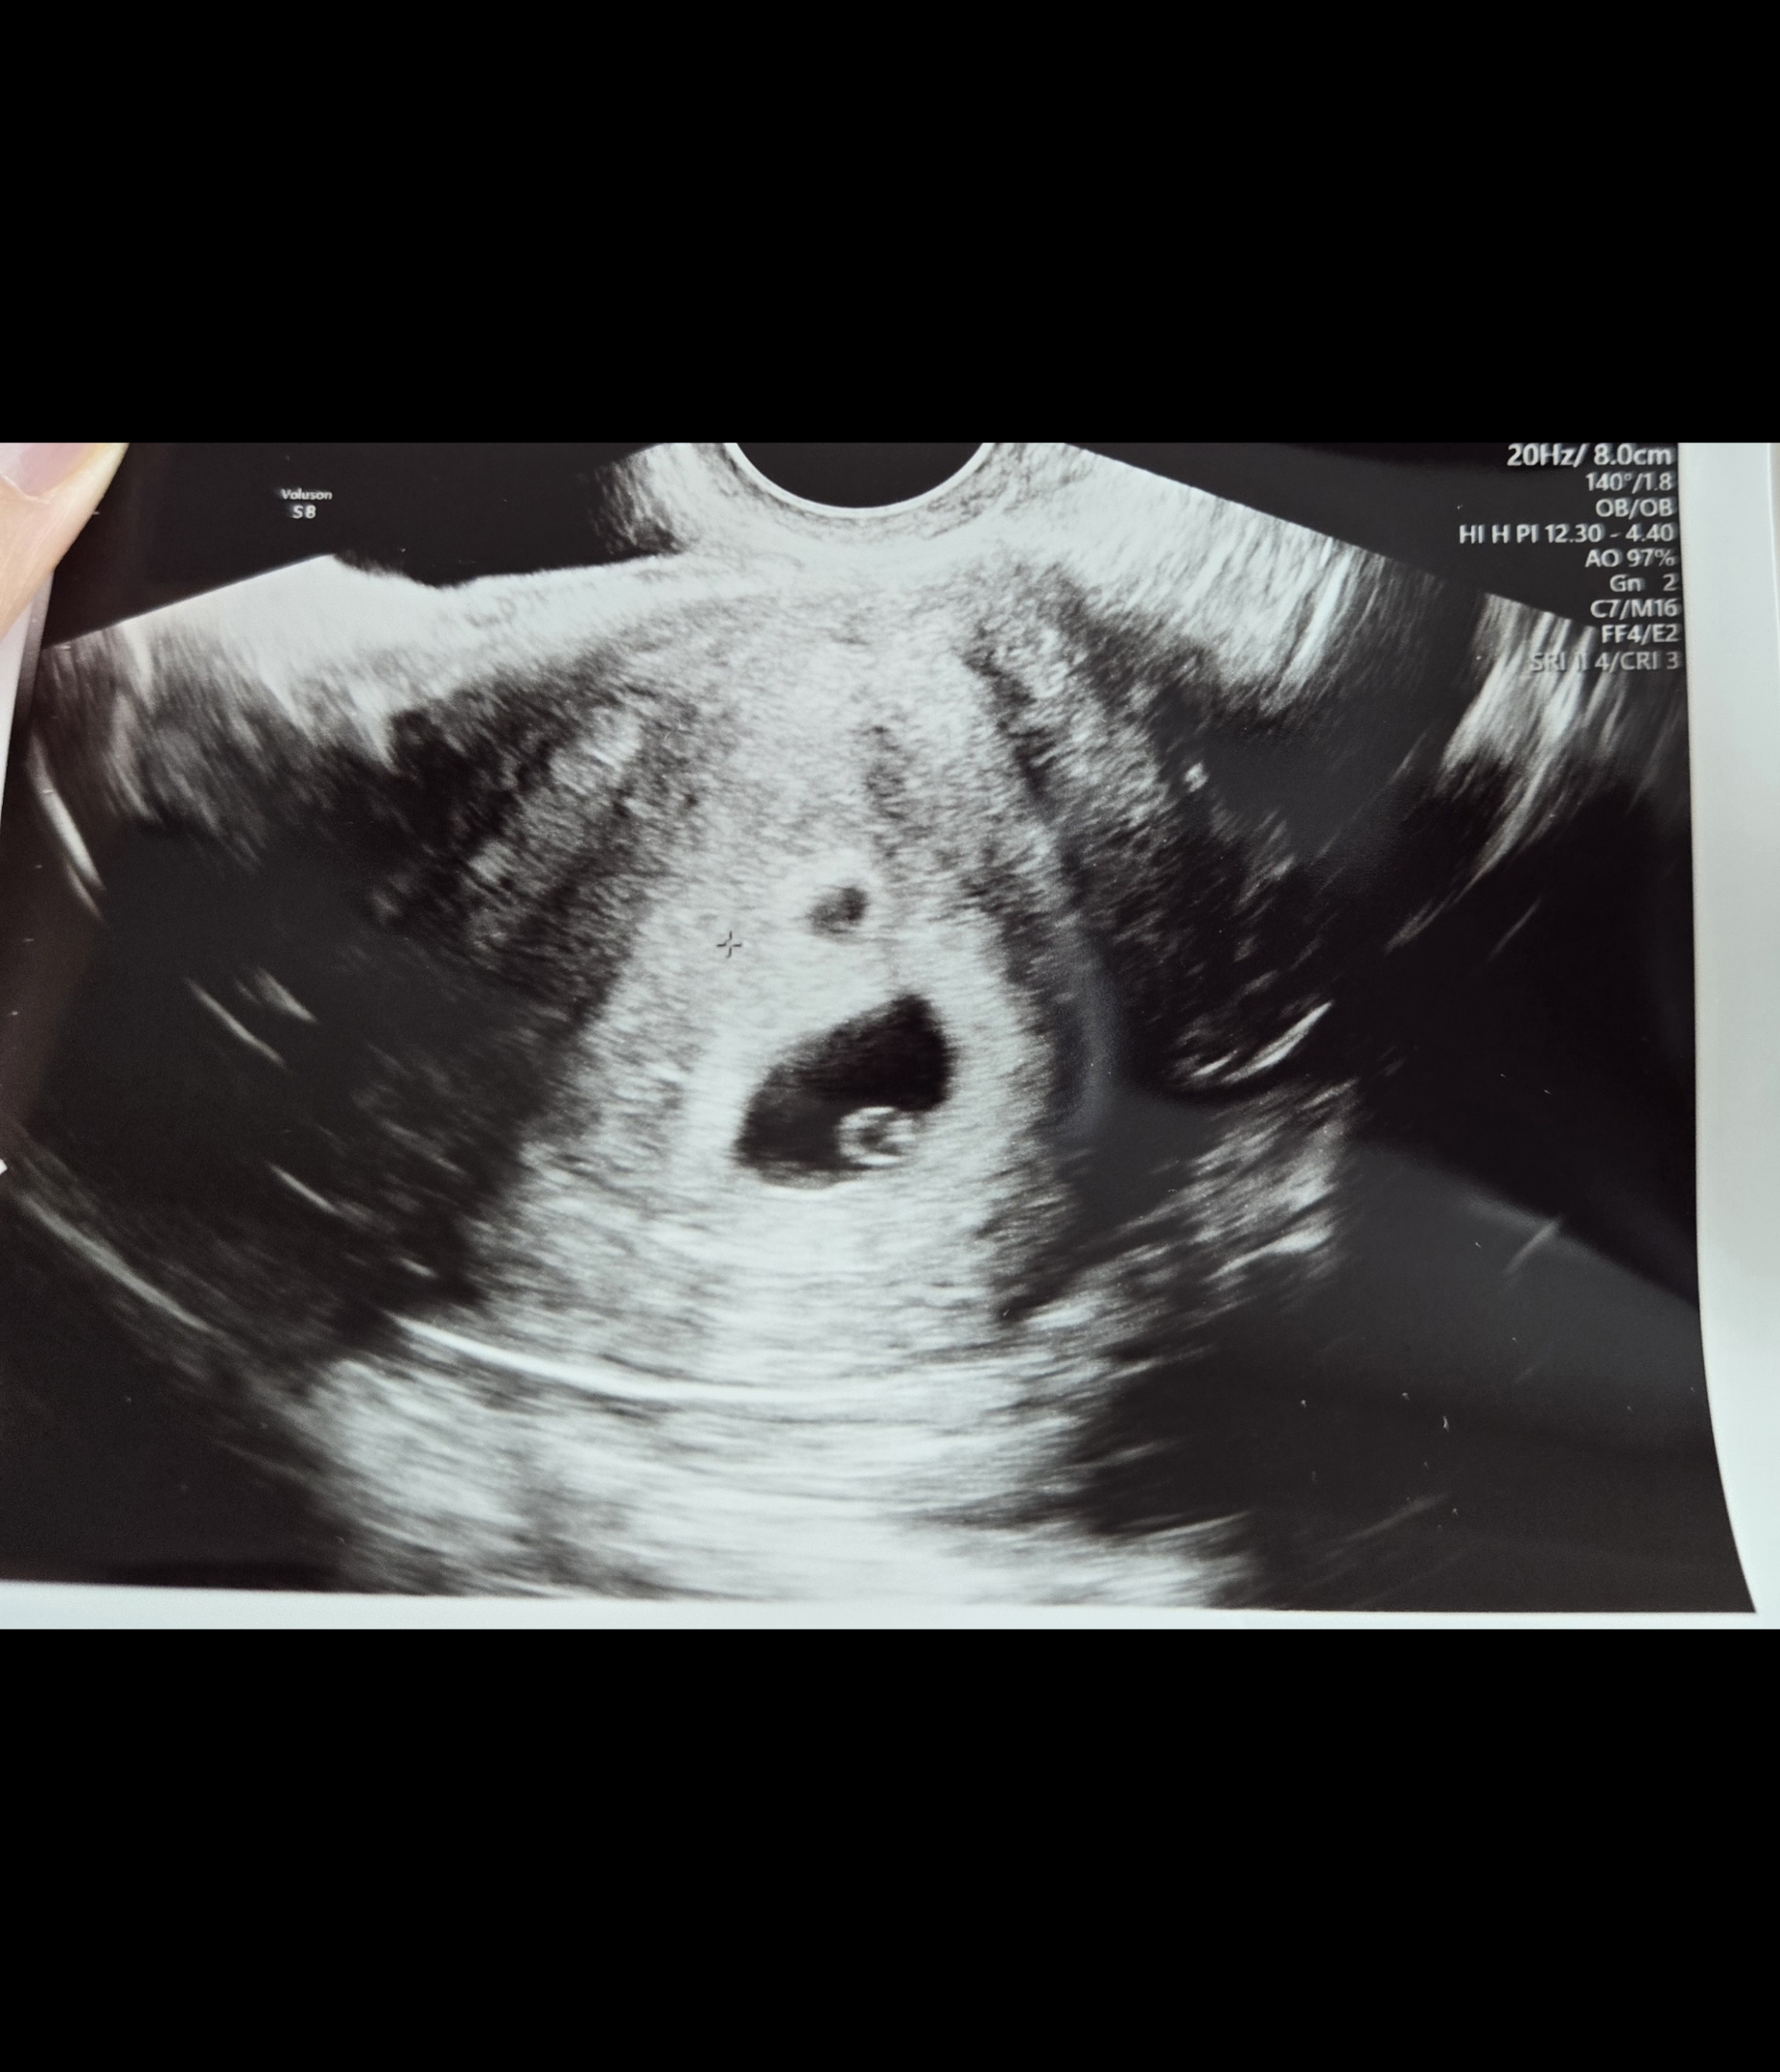

| 가슴 떨리는 임신 이야기를 공유해 주세요. | 4월 2일 난자 채취 후, 컨디션 회복을 위해 잠시 쉬어가는 시간을 가진 뒤 5월 31일에 5일 배아 2개를 이식했습니다. 그중 한 개가 찰싹 달라붙어 임신에 성공했을 때 정말 감격스러웠습니다. |